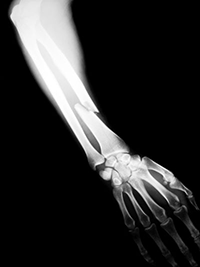

X-rays are a form of electromagnetic radiation, similar to visible light. Unlike light, x-rays have higher energy and can pass through most objects, including the body. Medical X-rays are used to generate images of tissues and structures inside the body. If X-rays traveling through the body pass all the way through to an X-ray detector on the other side of the patient, an image will be formed that represents the “shadows” formed by the objects inside of the body.

- Detecting a range of health problems including broken teeth and/or bones, bone changes or abnormalities, herniated discs in the spine, scoliosis and other spine curvature conditions, osteoarthritis, infections (e.g. pneumonia or other lung infections), certain tumors and other abnormal masses, kidney stones, calcifications, foreign objects, or dental problems.